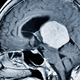

Britanec je leta spregledoval simptome, ki so kazali na tumor na možganih, dokler ga ni napad prisilil v nujno zdravljenje. Kot poroča index.hr , je 35-letni Craig Alexander več let … · Vizita.si · 1d

motnje vida vrtoglavica simptomi tumorja glavobol tumor na možganih objavi tvitaj